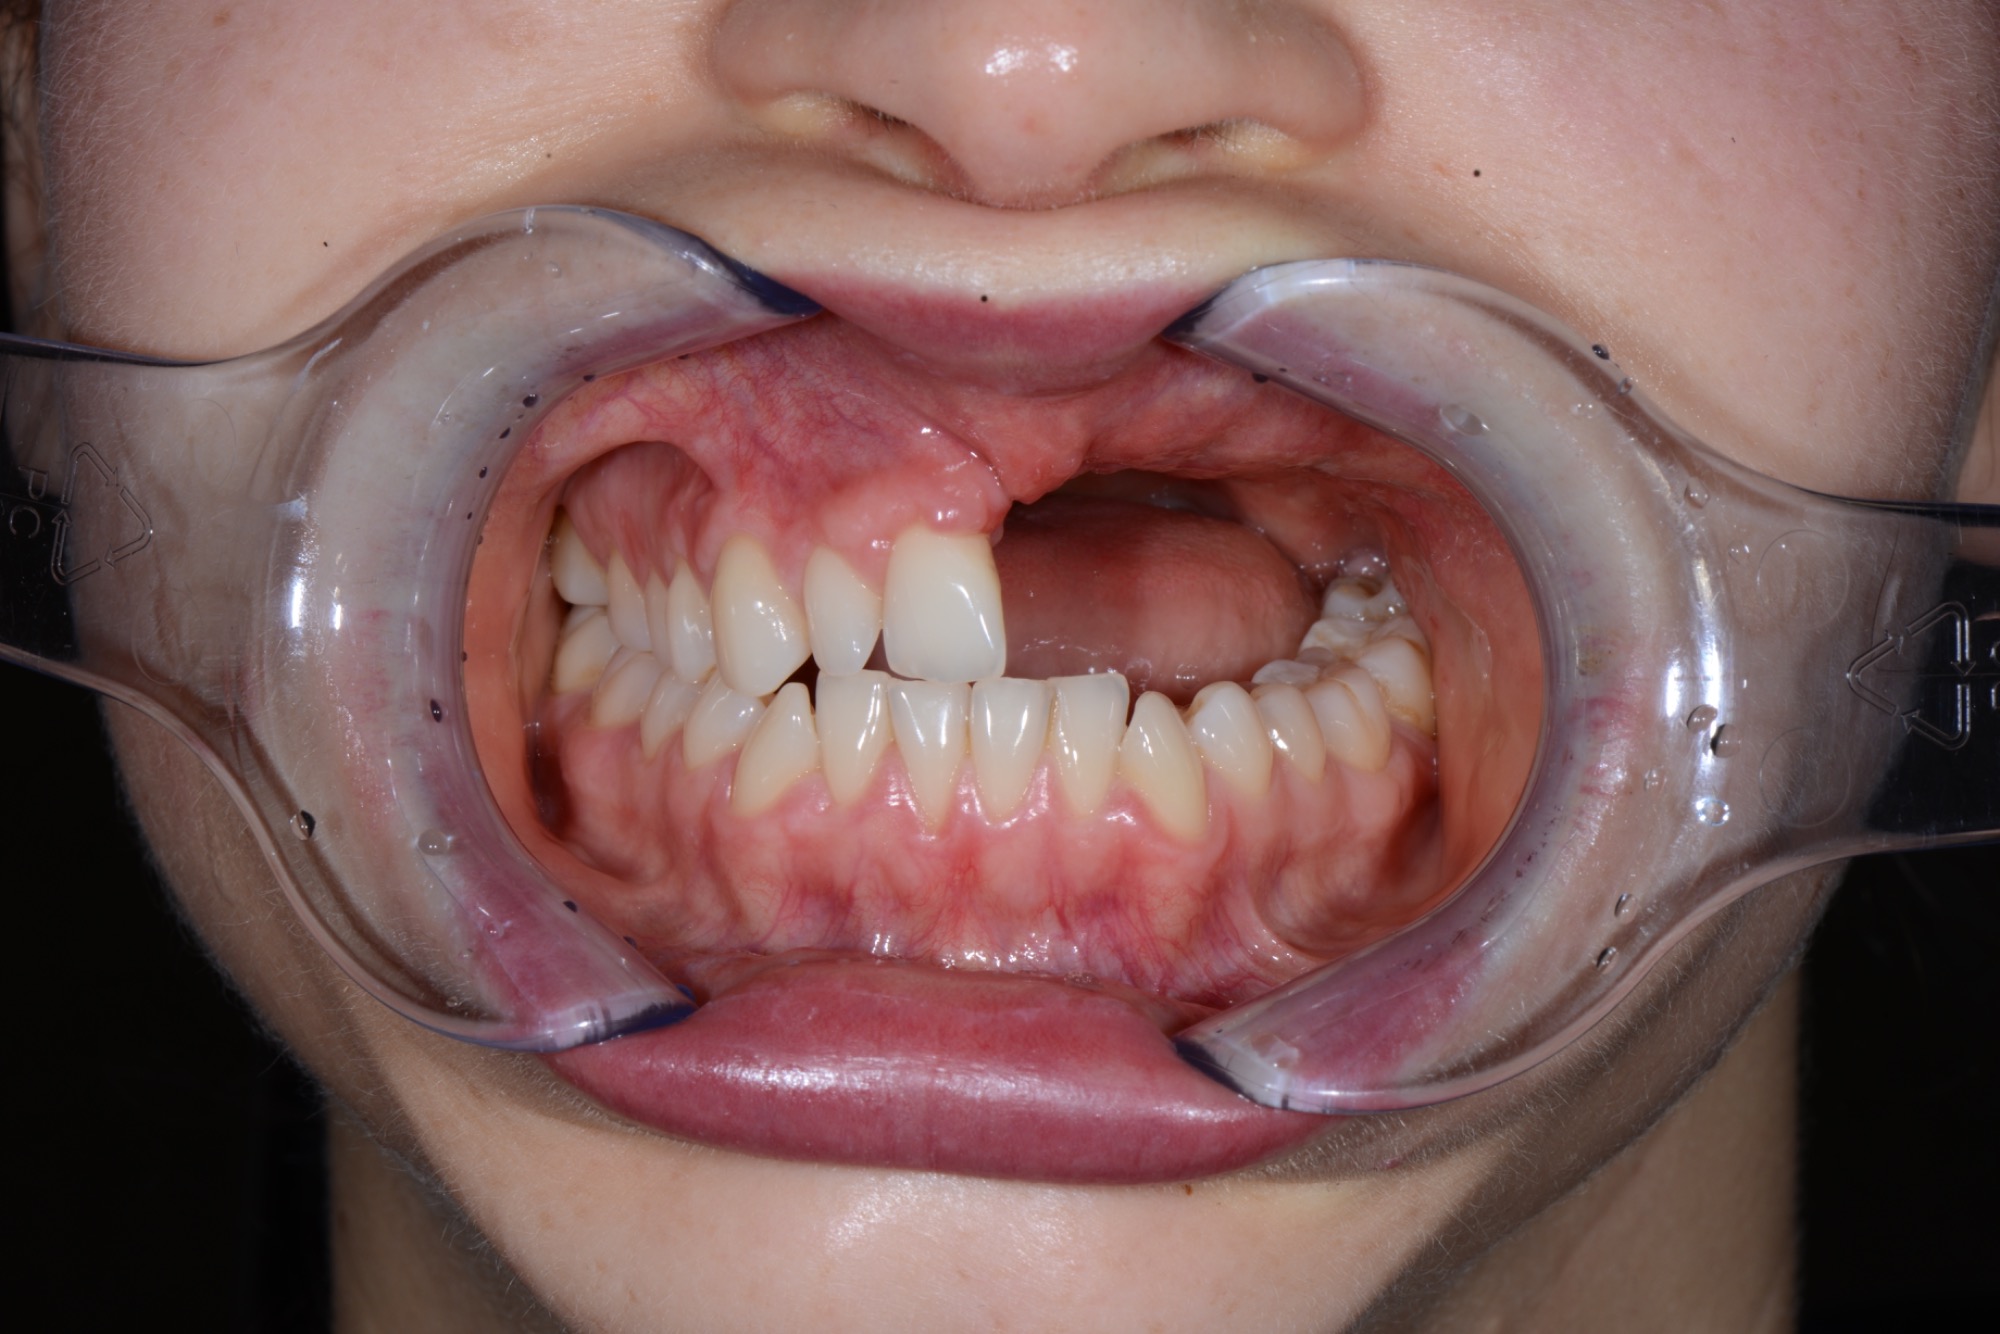

Teleskopierende Oberkieferbrücke mit Vorher- und Nachher-Situation des Patienten.

Teleskopierende Oberkieferbrücke. Wie die eigenen Zähne, aber einfach zu reinigen.